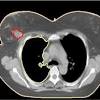

What Does Breast Cancer Look Like On A Ct Scan / Breast Cancer Radiation Planning Imaging Technology News - High risk of breast cancer.. Learn the stage of your cancer. Your doctor may recommend a breast mri scan if you have a diagnosis of breast cancer to determine the extent of the cancer. At left is a ct scan, while the center image is from a pet scanner. If your doctor suspects that you have cancer near your abdomen, they may recommend an abdomen ct scan. Ct, mri, and pet scans can also tell if your cancer spread.

Finding breast lumps and seeing change in the size and shape. Ct scans can help doctors: This test is most often used to look at the chest and/or belly (abdomen) to see if breast cancer has spread to other organs. Leak or rupture of a breast implant. With cancer cells, they appear as bright spots due to its higher metabolic rate compared to normal cells. A ct scan is a safe test for most people but like all medical tests it has some possible risks. As you probably know, a ct scan is one of several imaging techniques—this one primarily for looking at organs. Ct scans can be misread or misinterpreted. This helps radiologists identify areas where cells are suspiciously active, which can indicate cancer. As other answers have stated, what ct (and mri, and ultrasound) can show is the overall size of the lymph nodes, and in some cases how much blood supply they have. They may also use it to learn more about the cancer after they find it. Pet scan for breast cancer. If you have a condition like cancer, heart disease, emphysema, or liver masses, ct scans can spot it or help doctors see any changes.

Imaging and lobular breast cancer. When a breast cancer has been diagnosed, some people have a ct scan of their chest and tummy (abdomen) to stage the breast cancer. 4.9k views reviewed >2 years ago What does breast cancer look like? Your doctor and radiographer make sure the benefits of having the test outweigh these risks. Controversy continues to surround the question of whether ct and bone scans should be standard in evaluating patients for these metastases, or whether integrated pet/ct scanning might. To help you prepare, here's a look at what to expect. With cancer cells, they appear as bright spots due to its higher metabolic rate compared to normal cells. It is common for patients to receive a diagnosis for cancer of unknown primary. Ct scans can be misread or misinterpreted. The big problem with imaging is that we know, with certainty, that we can't usually. Combining a pet scan with an mri or ct scan can help make the images easier to interpret. As you probably know, a ct scan is one of several imaging techniques—this one primarily for looking at organs.

This test is most often used to look at the chest and/or belly (abdomen) to see if breast cancer has spread to other organs. If the cancer is thought to have spread, doctors can use imaging tests (tests that create pictures of the inside of the body) to help find out if or where a cancer has spread. They may also use it to learn more about the cancer after they find it. We'll show you breast cancer pictures to help you identify any physical traits of the condition. Benefits of a ct scan.